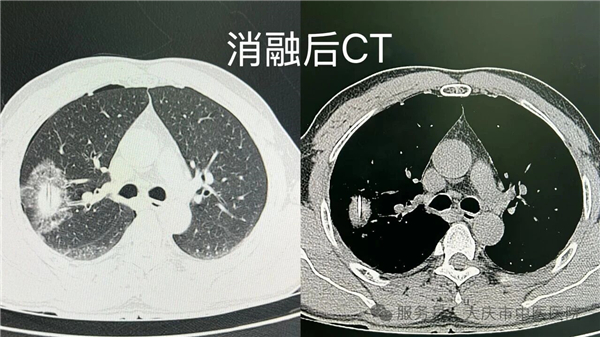

近日,在我院肺结节门诊牵头下,微创介入科联合 CT 室,成功开展一例肺结节同步病理活检与射频消融诊疗术。该技术在局部麻醉下,通过微创方式,同步完成病理活检取样与射频消融治疗,术中患者生命体征平稳,术后恢复良好。

本次开展的同步诊疗技术,在 CT 精准定位下,通过消融针到达病灶区域实施消融治疗,并通过同一通道获取组织标本进行病理检查,实现诊断与治疗环节的紧密衔接,有助于缩短诊疗周期,减少多次操作可能带来的相关风险。该技术的成功开展,是我院多学科协作及学科群建设的一次实践,为肺结节诊疗提供了新的技术选择。